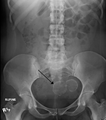

-

A very large (9 cm) fibroid of the uterus which is causing pelvic congestion syndrome as seen on CT